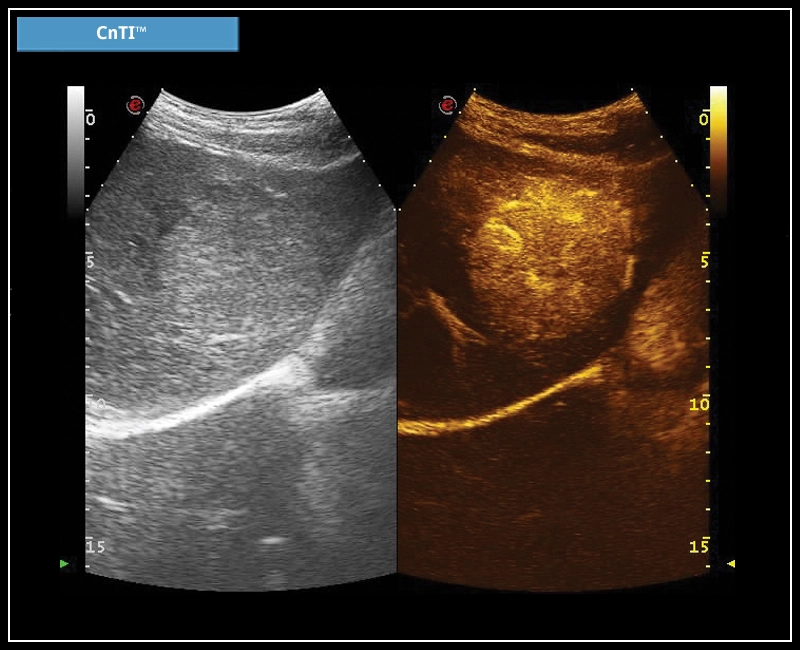

MyLab™Omega eXP - CnTI™

MyLab™Omega eXP - CnTI™